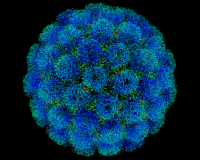

Обратим внимание на сообщение главного внештатного специалиста Минздрава России по инфекционным болезням Владимира Чуланова. Он говорит о том, что стабилизации ситуации с коронавирусом в России нужно ожидать приблизительно через две недели. Вводимые меры дают результат с отставанием.

Инфекционаст говорит, что нужно наблюдать за ситуацией, изучая меняющуюся статистику.

Чуланов напомнил, что с момента ухода школьников на каникулы, а некоторых сотрудников организаций - на удаленку уходит не так много времени с точки зрения развития эпидемической ситуации.

Интересно мнение Натальи Пшеничной. Она является заместителем директора по клинико-аналитической работе ЦНИИ Эпидемиологии Роспотребнадзора. Она сообщила том, что Россия уже, вероятно, приближается к пику по числу новых случаев коронавируса, которые выявляются за сутки.

В этой ситуации не стоит ожидать более 20 тысяч новых случаев COVID-19 на протяжении суток.

На протяжении последних суток в РФ зафиксировали 15 982 новых случая COVID-19.

Это рекордные показатели в России на период пандемии.